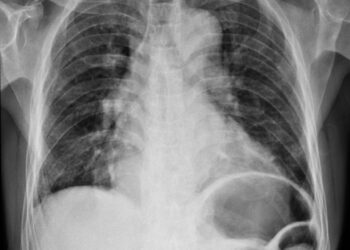

Kairiojo prieširdžio padidėjimas (KPP): simptomai, priežastys ir gydymas